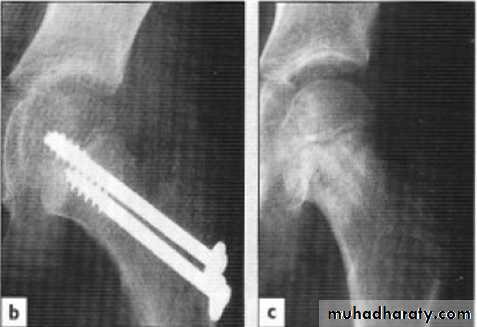

The fracture usually runs diagonally from the greater to the lesser trochanterKyle classification

Treatment:These fractures almost always treated by early internal fixation although they unite quiet easily by conservative treatment.

• Malunion: coxa vara (neck shaft angle <135o)

• avascular necrosis treated by partial or total hip replacement.

• Non union treated either by (ORIF + bone graft ) or hip replacement.